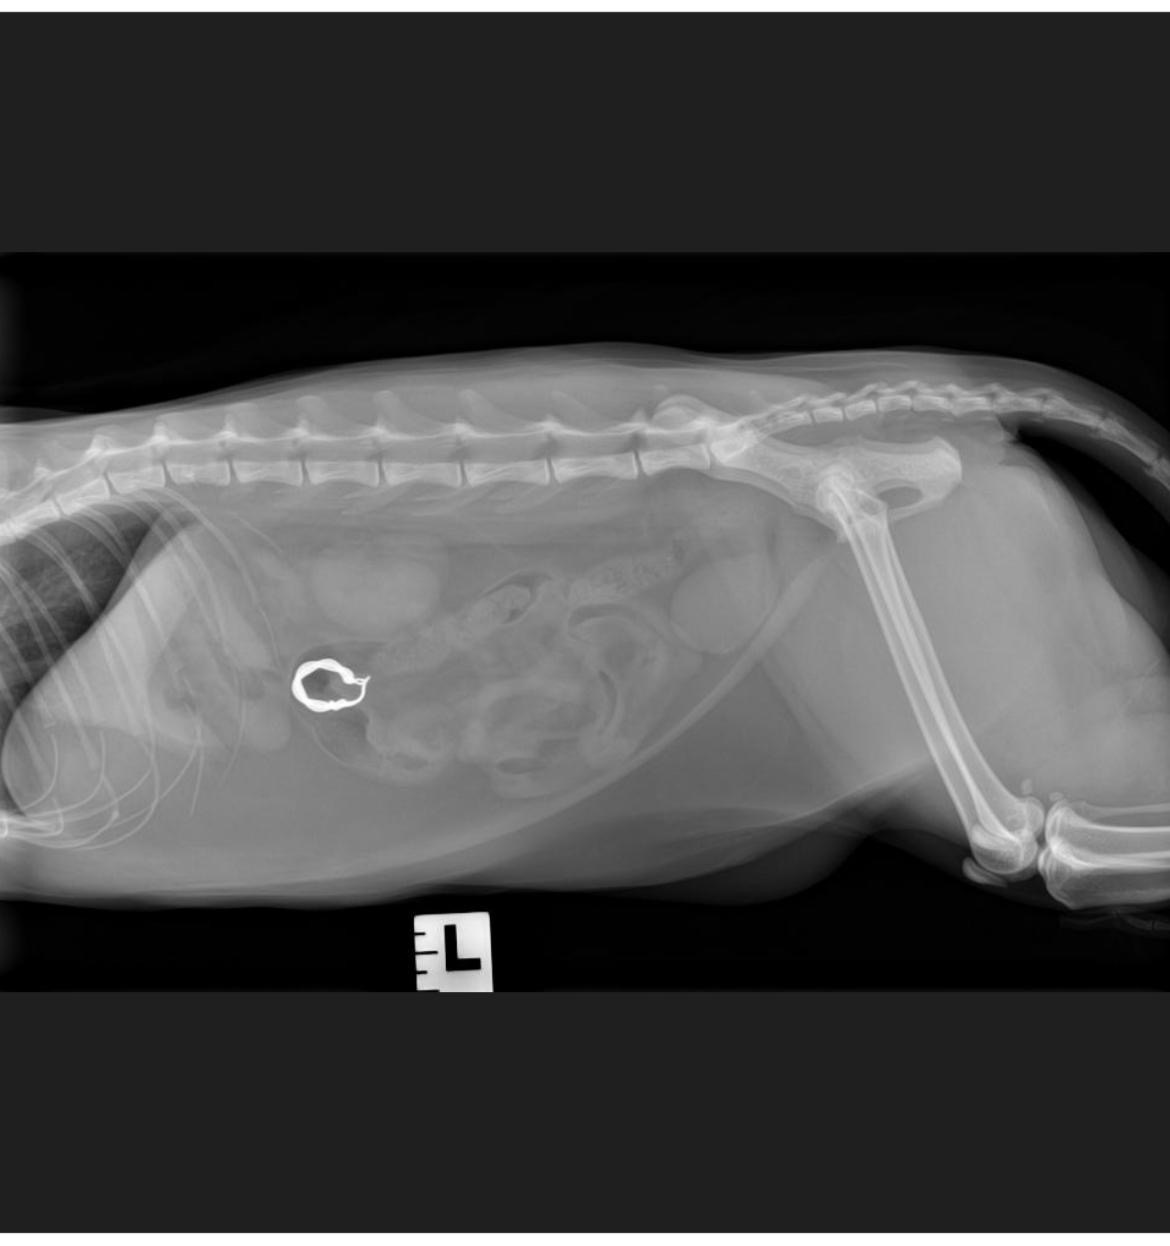

Hello, my name is Gloria and I’m in desperate need of your help! A couple of weeks ago our beloved cat, Tipsy, ate an earring and after days of medications and daily X-rays, she received a surgery as the situation was becoming too dangerous for her health. Everything seemed to go well until the 4th day post-surgery when she started looking off and all of a sudden started loosing liquid and smell very bad from her stitches. We obviously took her to the animal hospital right away cause it was a weekend evening. Even though we took very good care of her, gave her her meds and provided a safe and clean environment to rest on, she developed an internal infection that almost killed her. Because it was internal and very bad, she had to stay overnight to receive IV antibiotics and go under surgery again in order to understand the gravity of the situation, clean her and make sure it won’t happen again. Unfortunately a few days after this, a couple of her stitches broke, due to the bacteria accumulated around them internally. Her intestines almost fell out and we had to rush her to the hospital once again where she stayed for few more days under observation. We barely had the money to cover her first surgery, and we have now paid a total of 4k. We had a baby 6 months ago and for previous health reasons and a complicated pregnancy, I’m not on maternity leave/EI. We only live with one income and these vet’s bills are just too much for us right now.